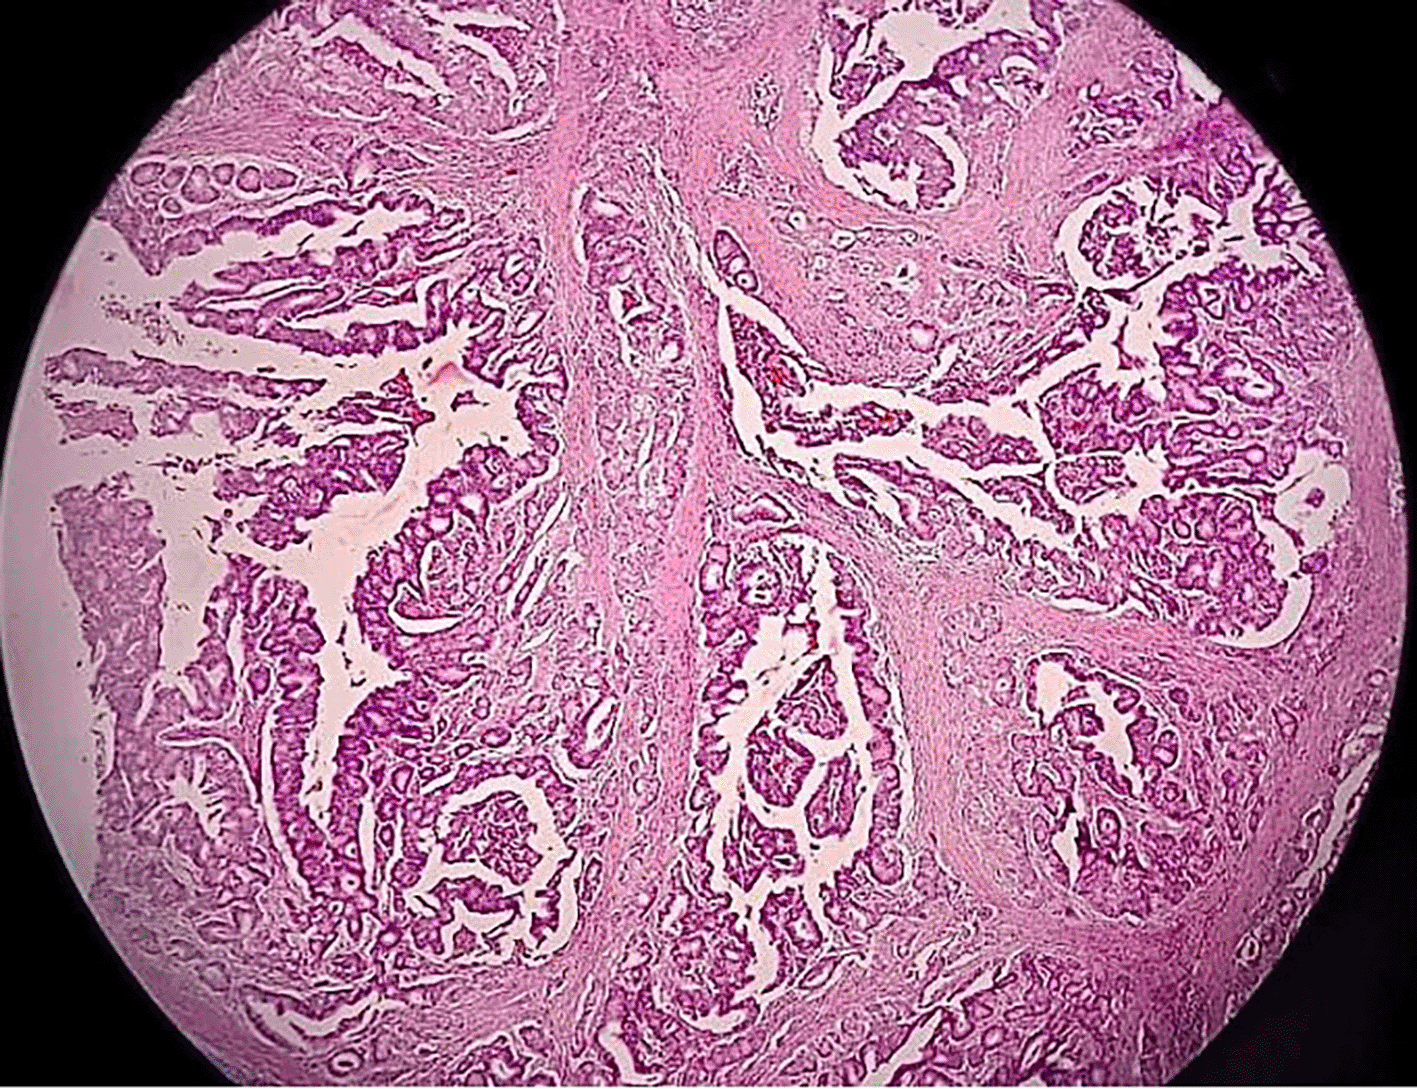

The patient was scheduled for a cystoscopy and urethral mass excision two days later. Cystoscope was inserted through the cystostomy access, showing a tumor infiltration to the anterior wall of the bladder approximately 2 cm from the bladder neck ( Figure 3). Due to highly suspicious lesions of malignancy based on visual, endoscopic, and imaging appearance, we didn’t perform preoperative biopsy and proceeded to definitive surgery. Radical urethrectomy and partial cystectomy were then performed through a transurethral approach with antegrade cystoscopy guidance. This method was used to make sure the tumor completely resected since we do not have frozen section facilities in our hospital. The excision was extended to the bladder neck and a portion of the anterior segment of the bladder wall which infiltrated by the tumor. We decided to do the bladder preservation and bladder neck reconstruction using remaining anterior bladder wall with the intention to facilitate voiding through the orthotopic site with a Foley catheter, thereby avoiding the need for a permanent suprapubic diversion. The tumor-free bladder punctum was pulled through the former urethral orifice and the bladder muscle was sutured to the urogenital diaphragm using 3-0 Vicryl, interrupted in eight directions ( Figure 4). The bladder mucosa is sutured to the vulvar mucosa, similar to a vesicostoma with 5-0 Chromic, interrupted in eight directions. After the suturing was done, we re-evaluate the bladder with cystoscopy to make sure the ureteral orifices remain intravesical. The surgery was performed without complications and the patient was discharged home within 5 days using silicone foley catheter. The silicone catheter is left in place for 1 month to assure good healing and avoid stenosis. The pathology report revealed 5×4 cm sized pT4 urethral adenocarcinoma with bladder infiltration, clear surgical margins, and enteric type histologic subtype ( Figure 5). Neither radiation nor chemotherapy were administered since the patient has negative node and no distant metastasis. At 1 month follow-up, the patient was in continuous incontinence status. This condition is expected since the sphincter was also resected during the surgery as the tumor already infiltrated the anterior bladder. But with the use of silicone catheter, we can avoid any leak and patient still can void timely through regularly clamp catheter. We didn’t performed uroflowmetry and PVR evaluation since the patient is incontinent without foley catheter. We aimed to maintain the catheter for long term usage to increase the patient quality of life. At the 1-year follow-up, the patient reported satisfaction with the outcome of the surgery and her quality of life. The CT scan evaluation showed no signs of recurrence or metastasis.

Enteric/mucinous (intestinal-type) subtype often show abundant extracellular mucinous and clusters of neoplastic cells floating in mucin pools. It resembles colorectal adenocarcinoma histologically and immunohistochemically, but can be distinguished by lack of nuclear β-catenin and clinical context.9